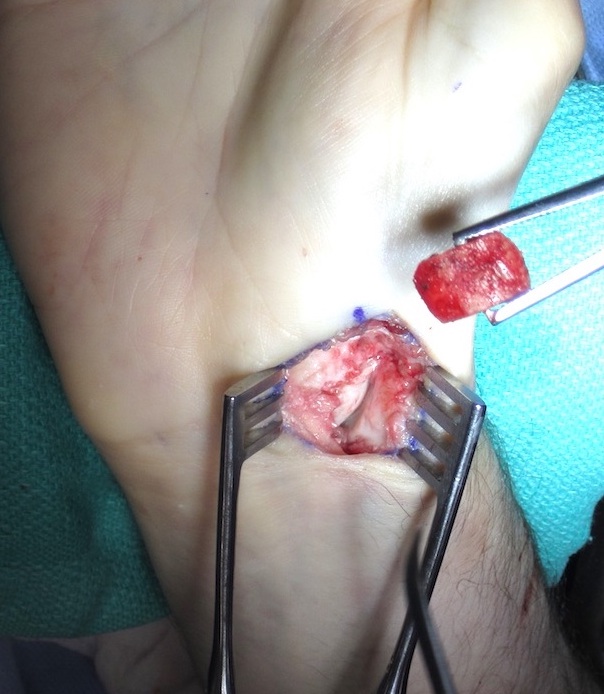

Post scaphoid ORIF

Technique

Volar approach

- clean fracture site of fibrous tissue with burrs if needed

- reduce deformity

- do not disrupt dorsal cortex

- place bone graft

- insert screws +/- plate